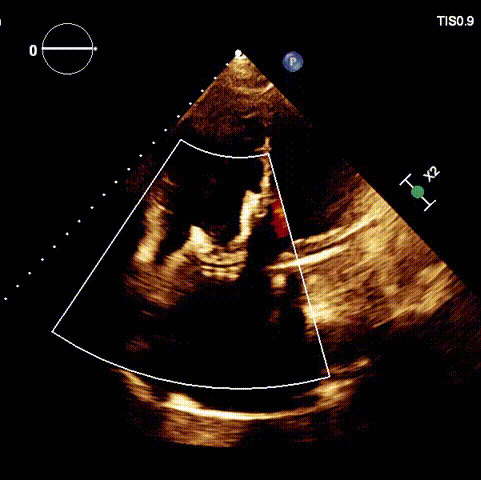

術后超聲

近日,廈門大學心血管病醫(yī)院王焱教授帶領的結(jié)構性心臟病團隊,成功應用LuX-Valve Plus經(jīng)血管三尖瓣置換系統(tǒng),為一例高危三尖瓣重度反流患者開展經(jīng)血管三尖瓣置換手術。此次手術系LuX-Valve Plus人工瓣膜在福建省的首例植入,手術過程順利,術后患者三尖瓣反流顯著改善,標志著由葛均波院士團隊作為主要研究者的LuX-Valve Plus經(jīng)血管三尖瓣置換系統(tǒng)全國多中心臨床研究的再一次成功實踐,為三尖瓣介入治療的醫(yī)學循證打下了夯實的基礎。 、

手術在全麻狀態(tài)下開展,海軍軍醫(yī)大學附屬長海醫(yī)院陸方林教授與廈門心血管病醫(yī)院王焱院長共同上臺,為患者進行手術。此次手術采用經(jīng)右側(cè)頸靜脈入路的方式將輸送器送入患者心臟內(nèi),在TEE及DSA引導下調(diào)整輸送器頭端角度,使得輸送器與三尖瓣瓣環(huán)平面垂直。在輸送器進入右心室后釋放室間隔錨定裝置,而后釋放瓣葉夾持件(2個耳片結(jié)構)成垂直狀態(tài)。在TEE及DSA確定夾持件固定至三尖瓣葉根部且位于右室側(cè)后釋放人工瓣心房側(cè)盤片。隨后調(diào)整瓣膜同軸性以及室間隔錨定件位置(貼合室間隔),前推藏針管并固定,進而釋放室間隔錨定裝置,并再次確認瓣膜位置、穩(wěn)定性及同軸性,合攏輸送鞘后撤出輸送器,完成LuX-Valve Plus人工三尖瓣瓣膜的植入。